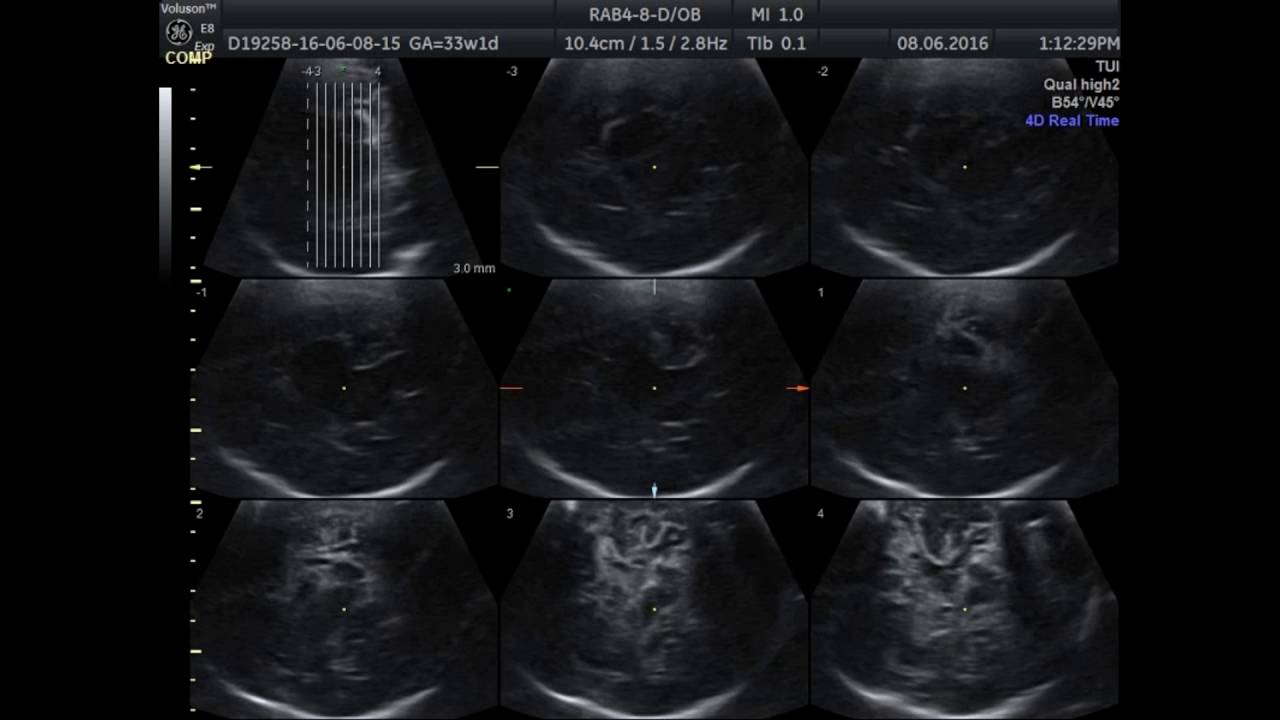

У детей до 3 лет вена Розенталя хорошо лоцируется и при заднем доступе на уровне затылочного бугра парасагиттально, и снаружи от вены Галена на глубине 62-65 мм .

Нормальная скорость кровотока у детей до 1 года в вене Галена 4-18 см/с . Галенова вена может быть двух различных форм: магистральная и рассыпная . Первая из них имеет длину ствола 1,5-3 см, и не меньше семи протоков . Сосуды по данному типу строения чаще всего встречаются у лиц с долихоцефалическим черепом .

Вена галена скорость норма у новорожденных . Ультразвуковое исследование позволяет изучить работу и строение внутренних органов .